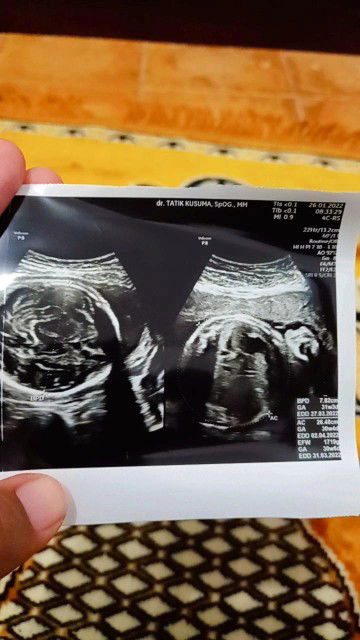

hptp dan usg berbeda

hptp 8 minggu usg msh 6 minggu 3 hari,,, bner yg mna ya bun?

tapi aku pernah baca harusnya beda usg sama beda hitungan HPHT gag sampai sebulan kalau beda 2 minggu masih normal kalau udah beda sebulan mending periksa lagi mbak.

sma nih bun awalnya aku jg di bilang bidan puskesmas kehamilan skrng udh jalan 9 w ternyata aku pas usg msh 6w 3hari baru keliatan kantongnya

emang gitu bun gasesuai.. gapapa bun kalau aku si pas lahirnya lebih akurat usg